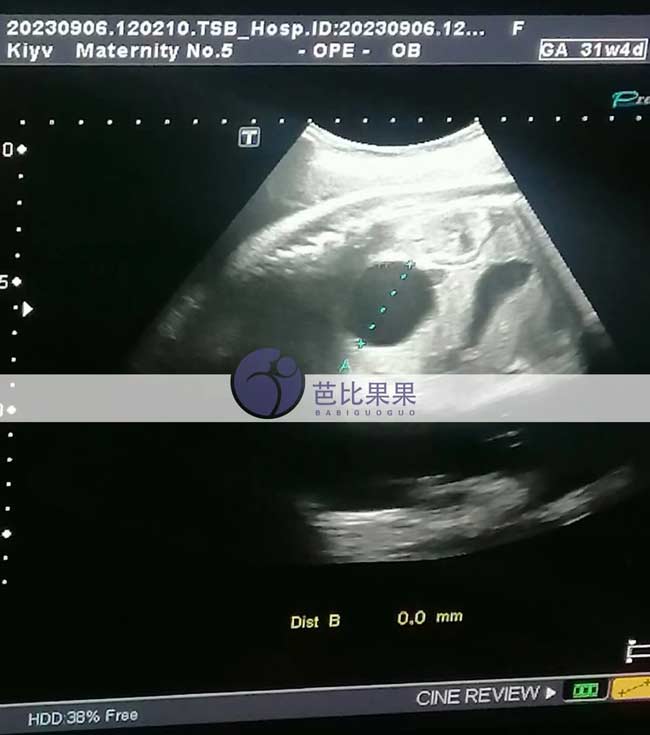

H女士家的乌克兰试管妈妈来医院做31周b超检查,胎儿已经长得蛮大了,期待他的到来